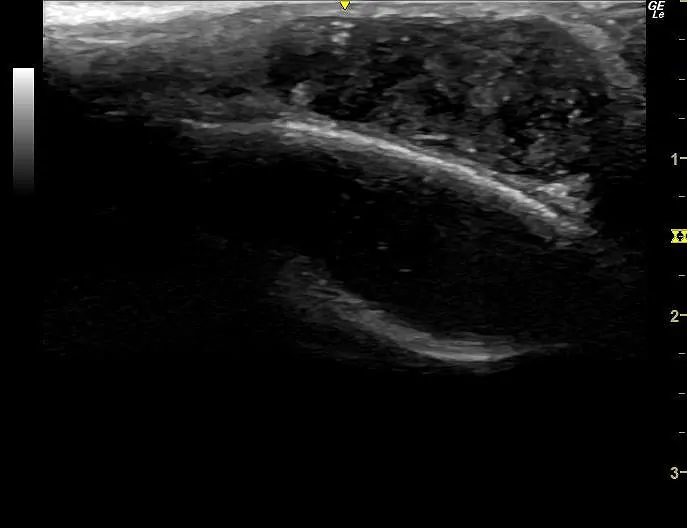

超音波検査では内部エコーが均一で被膜がはっきりした腫瘍が指摘できます。

頭蓋骨が真下にあるため、後方エコー増強ははっきりしませんが、正常の組織と比べてわずかに増強しているようでした。

頭部にできた粉瘤と診断しました。

超音波検査